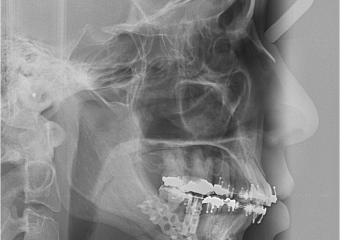

Telerradiografia final